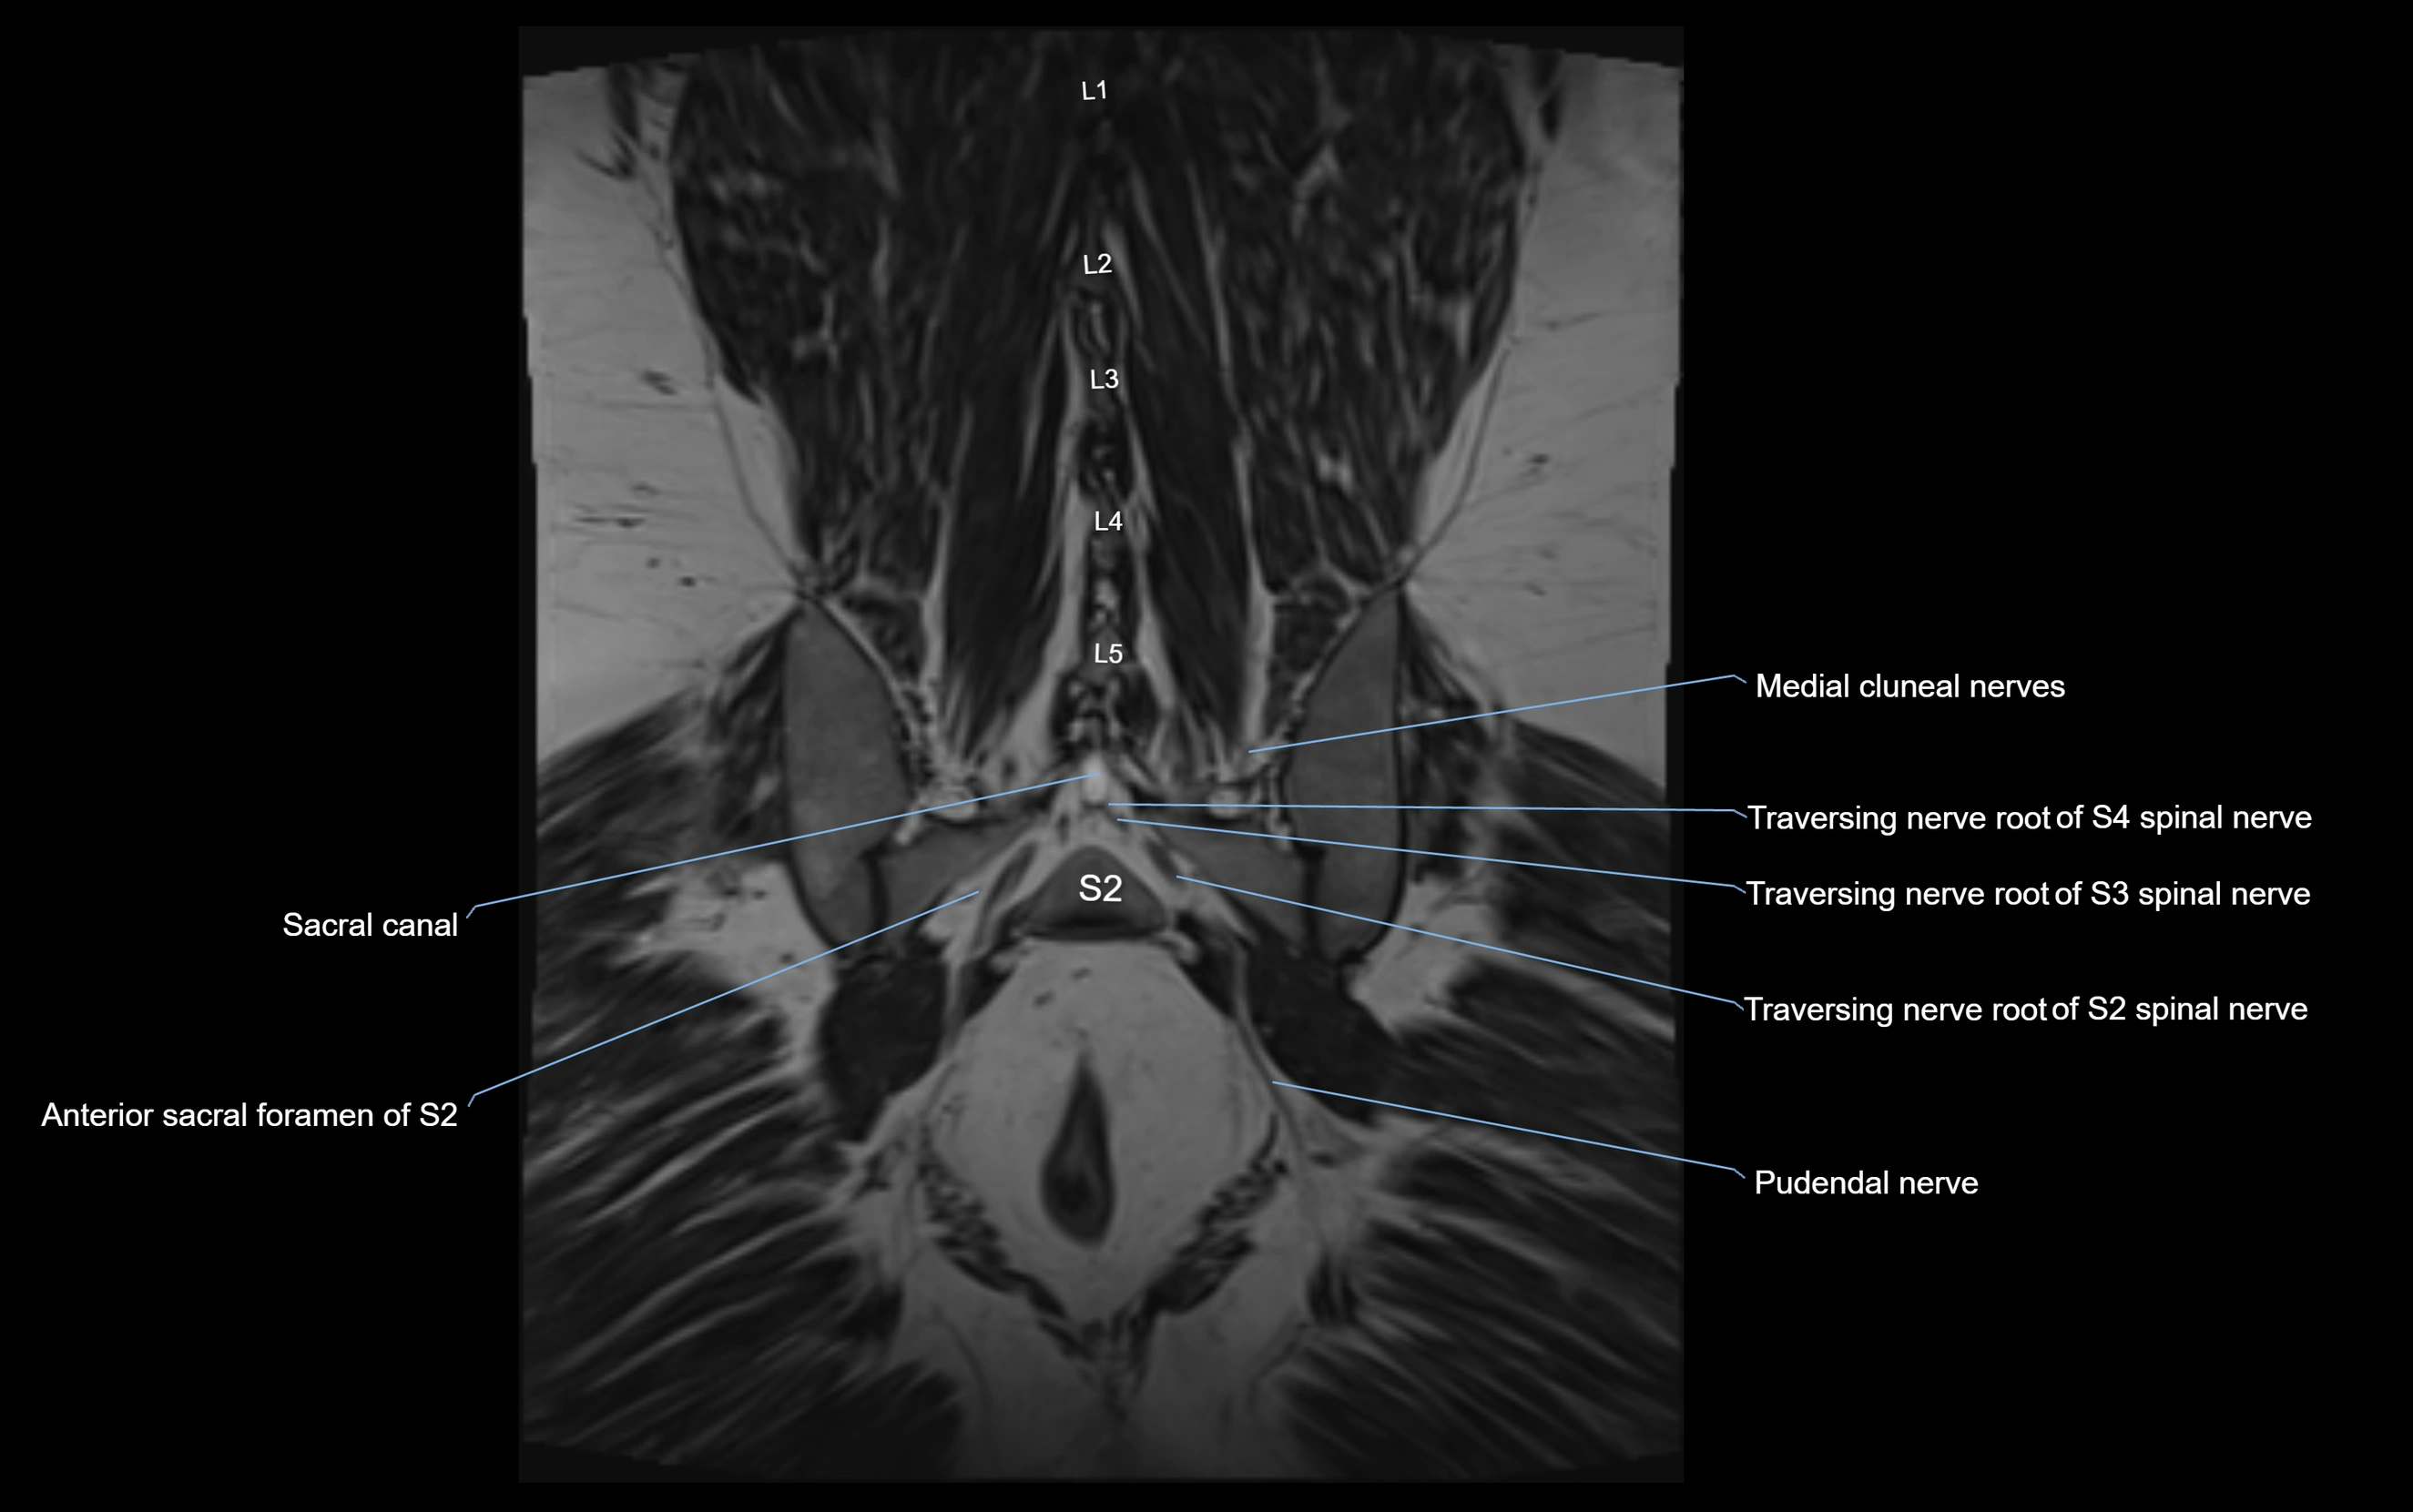

MRI Appearance

T1-weighted images:

• Nerve appears as a very thin low-to-intermediate signal intensity structure

• Surrounded by bright fat, aiding visualization

T2-weighted images:

• Nerve shows intermediate to mildly hyperintense signal compared to muscle

• Pathological involvement appears brighter

STIR (Short Tau Inversion Recovery):

• Normal nerve appears dark

• Inflamed or entrapped nerve appears bright hyperintense

T1 Fat-Sat Post-Contrast:

• Normal nerve enhances minimally

• Pathologic nerve (neuritis, entrapment, tumor infiltration) shows focal or diffuse enhancement

3D T2 SPACE / CISS:

• Nerve appears intermediate to mildly hyperintense compared to muscle

• Surrounded by bright fat or CSF, improving visualization

• Best sequence for mapping small pelvic nerves such as the anococcygeal

MRI image

image